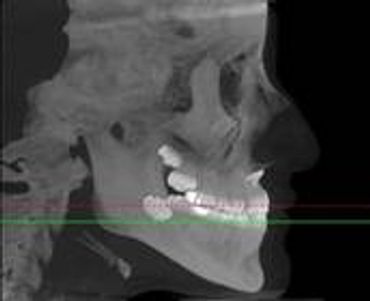

What is CBCT- Cone Beam Computer Tomography?

CBCT is a digital x-ray scanner specifically designed for scanning the head and jaws. The scanner rotates 360 degrees around the patient's head in a matter of seconds. The x-ray is a low energy fixed anode tube similarly used in panoramic machines. This method reduces radiation scatter common to most conventional x-rays. The cone shaped x-ray provides 360 views that can be presented in 2D image and 3D volume for advanced planning and diagnostic support.

[Why the need for a CBCT?]

This one scan provides more images than plain film conventional imaging, with complete visualization of the patient's entire maxillofacial region. These images clearly display TM disorders, impacted teeth, critical bone and tooth relationships, oral- nasal airways, para-nasal sinus, mandibular canal and difficult to see pathologies within one volume. The user friendly software system reconstructs true size, distortion free, high resolution images.

[Why is this better for patients?]

The CBCT scanner is fast, comfortable (nothing goes in the mouth), and painless for patients. It provides a complete set of maxillofacial images with less radiation than conventional orthodontic and medical type CT work-ups. CBCT now can re-create true size cephalometric and panoramic images, virtually eliminating the need for conventional orthodontic x-rays, so your patients will be comforted by the knowledge that you have all the information needed to evaluate and plan their treatment